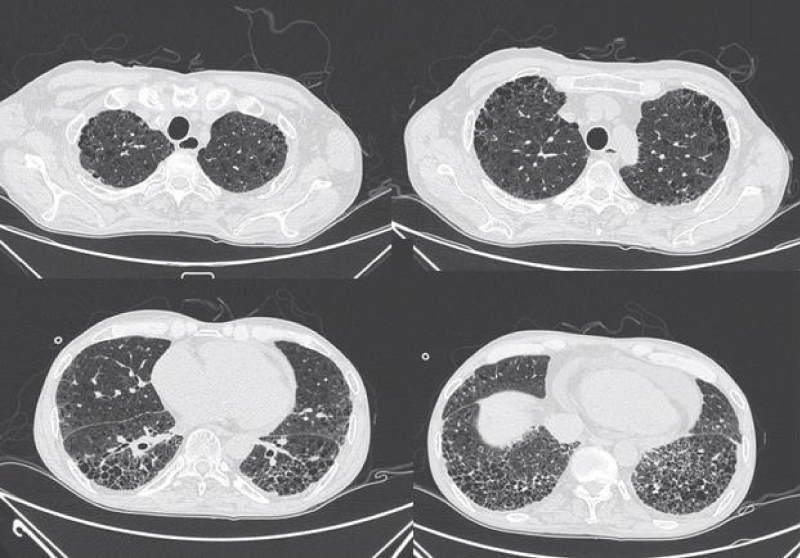

HRCT images

The most common presentation on HRCT were ground-glass opacities, showed 79.3% (92 patients). Secondly, 74.1% patients showed interlobular septal thickening, followed by reticular opacities(58.6%), intralobular interstitial thickening(45.7%), mediastinal lymph node enlargement(36.2%), nodules(30.2%), honeycomb cysts (29.3%), traction bronchiectasis(21.6%), stripes(17.2%), pleural thickening(14.7%), pleural effusion(10.3%), dilation of the esophagus(6.9%), emphysema(6.9%), bullae(5.2%), consolidation(5.2%), subpleural line(0.9%) (Figures 1-9).

Figure 8: Different levels HRCT images from a 54 year-old male considered as UIP pattern.

The most common pattern in SSc-ILD was NSIP, accounted for 71.6% (83 patients); secondly was UIP, accounted for 25.9%, and 3 patients presented consistent with LIP.

The pathological feature of usual interstitial ipneumonia(UIP) was heterogeneous appearance, showing an alternate distribution of interstitial inflammation, fibrosis and normal lung tissues and can see limits scar formation with dense fibrosis, lead to the destruction and cystic formation of the pulmonary parenchyma similar to honeycomb. On HRCT imaging, UIP appeared as reticular opacities and honeycombing mainly distributed around the lung and under the pleura, with or without traction bronchiectasis [20].